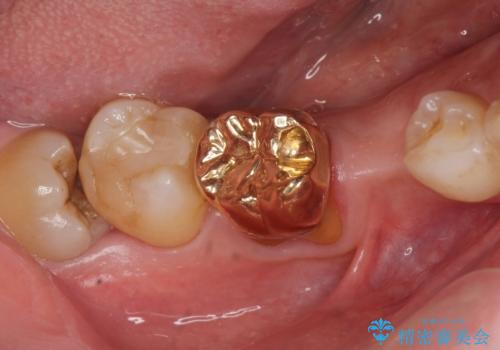

ゴールド(PGA)クラウンの自然な咬み心地とブリッジの審美的な仕上がりに喜んで頂けました。

モチベーションが上がり、ホワイトニングもご希望され補綴前に行いました。

右下の小臼歯(右下5)を他院で抜歯されたことを後悔されており、「はやくこの病院に来ていれば良かったなあ」とおっしゃって下さいました。

右下7:ゴールド(PGA)クラウン

右下⑥5④ブリッジ:オールセラミッククラウン スタンダード